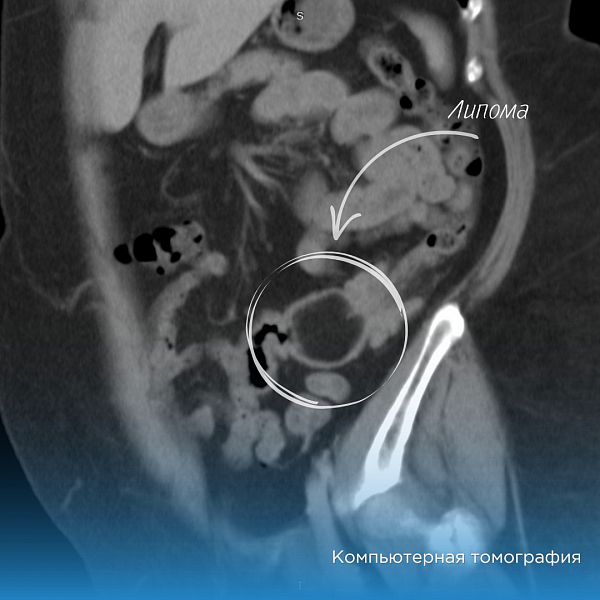

В Нижневартовскую окружную клиническую больницу поступила женщина с жалобами на боли в животе и нарушением стула. Исследования выявили у неё крупное подслизистое образование диаметром свыше 5 см, которое оказалось липомой.

Липома — это доброкачественное образование, которое развивается в подслизистом слое. Но, в случае пациентки, она смещалась вниз, что вызывало болевые ощущения.

Липома была большой и не проходила через сфинктеры толстой кишки. Специалистам пришлось разделить на фрагменты её внутри кишечника и извлекать по частям. Операция продолжалась два часа и завершилась успешно.